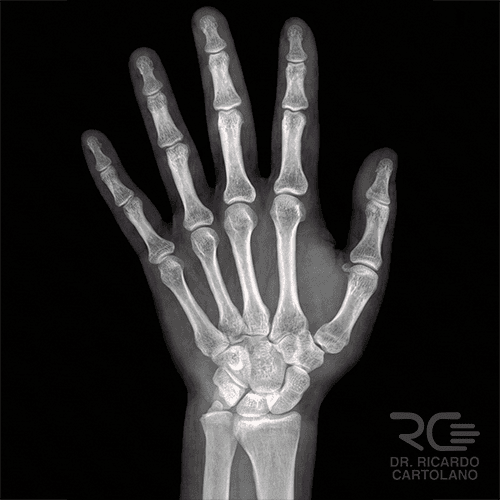

Radiografia (Raio-X)

É o exame inicial para quase todas as queixas. Fundamental para visualizar a estrutura óssea, identificar fraturas, avaliar o alinhamento das articulações e detectar sinais de desgaste (artrose).